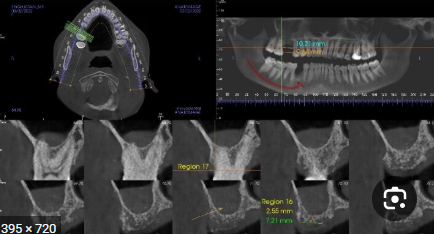

- How MSI Works:

- Uses LED or laser light at specific wavelengths (400–1000 nm) to assess tissue oxygenation, vascularity, and keratinization.

- Advanced algorithms analyze spectral signatures to differentiate malignant from benign lesions.